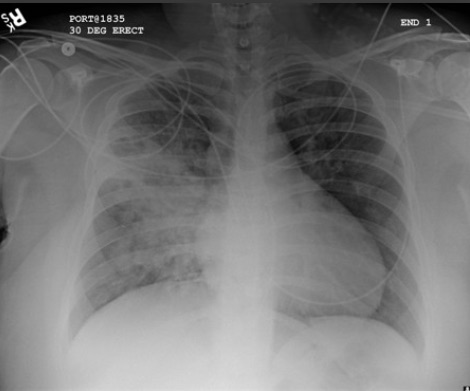

Radiografía de tórax que muestra neumonía cavitante en el lóbulo superior izquierdo

De la colección del Dr. Jonathan Bennett. Usado con autorización